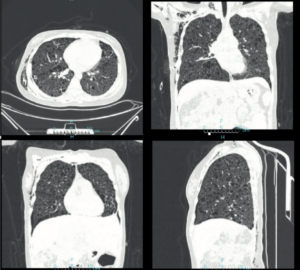

Figura 3.- TC de tórax de control a los 8 días del evento inicial en el que se observa resolución completa del neumotórax derecho y se demuestra una enfermedad quística pulmonar bilateral de pared fina, con distribución simétrica en el parénquima, compatible con linfangioleiomiomatosis. Existe resolución espontánea y completa de las bullas gigantes pulmonares izquierdas. Es evidente el enfisema subcutáneo en la pared torácica lateral derecha y cuello.

Figura 4.- La reconstrucción tridimensional muestra la presencia de múltiples lesiones quísticas distribuidas en los dos pulmones.